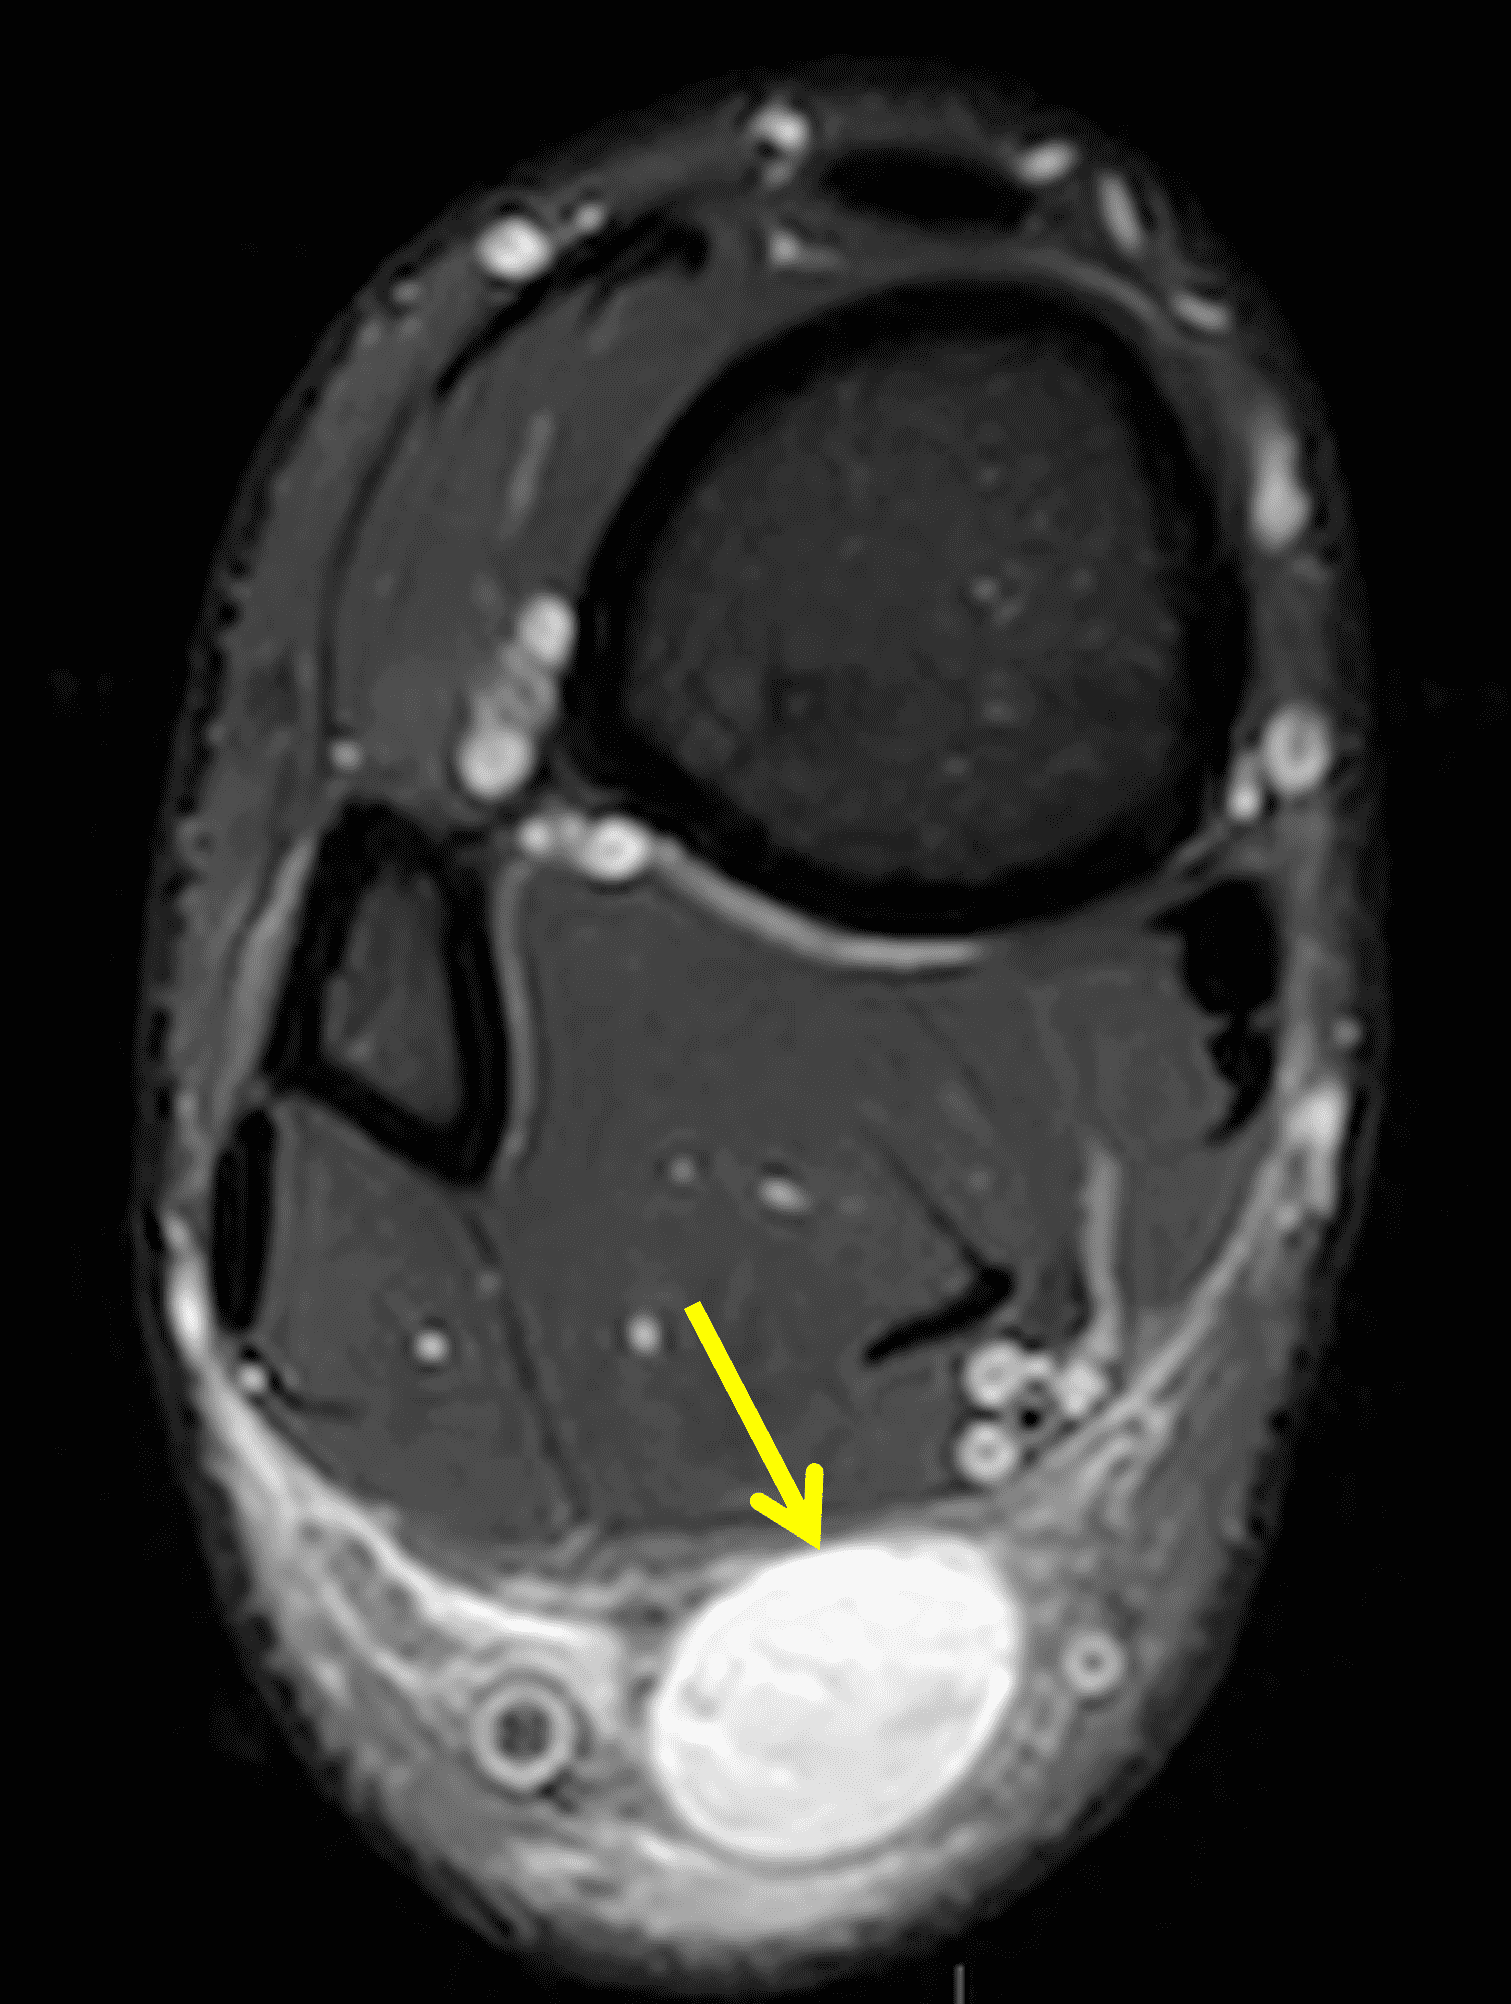

A 22 year-old male college football player presents with a “pop” and pain posterior to the right ankle during practice 1 week prior. He is unable to bear weight. Lateral radiograph (1A), sagittal fat-suppressed T2-weighted (1B), sagittal T1-weighted (1C), and transverse fat-suppressed T2-weighted images are provided. What is your diagnosis? What MRI findings affect clinical management decisions?

Figure 2: Complete Achilles tendon rupture. (2A) The lateral radiograph shows a thick and indistinct proximal Achilles tendon contour (arrows). (2B) A fat-suppressed T2-weighted image shows complete rupture of the tendon with a fluid-filled gap (yellow arrow) measuring 1.5 cm in length, located 10 cm cranial to the tendon insertion (blue arrow) and just distal to the edematous myotendinous junction (red arrow). The tear is superimposed on diffuse tendinosis. (2C) A sagittal T1-weighted image confirms the diffuse tendinosis. Fluid extends anteriorly into Kager’s fat pad (arrow) suggesting disruption of the anterior paratenon. (2D) A transverse fat-suppressed T2-weighted image through the proximal tendon shows no intact fibers (arrow), confirming the full-thickness rupture.